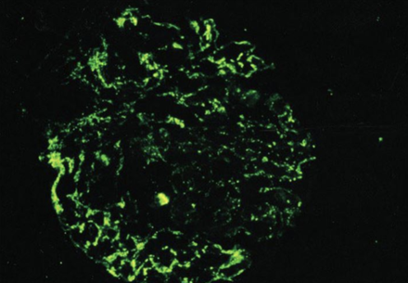

C3

An 8 year old boy is brought to the office due to acute facial puffiness. His mother reports that he has been fatigued and has had dark urine. The patient was treated for a skin infection 3 weeks ago but has no chronic medical conditions. Temperature is 97 F, BP is 140/94. PE shows periorbital edema and mild pitting edema along the ankles. Renal biopsy was performed and the sample is shown below.

The fluorescent areas on the slide most likely indicate the presence of which of the following substances?